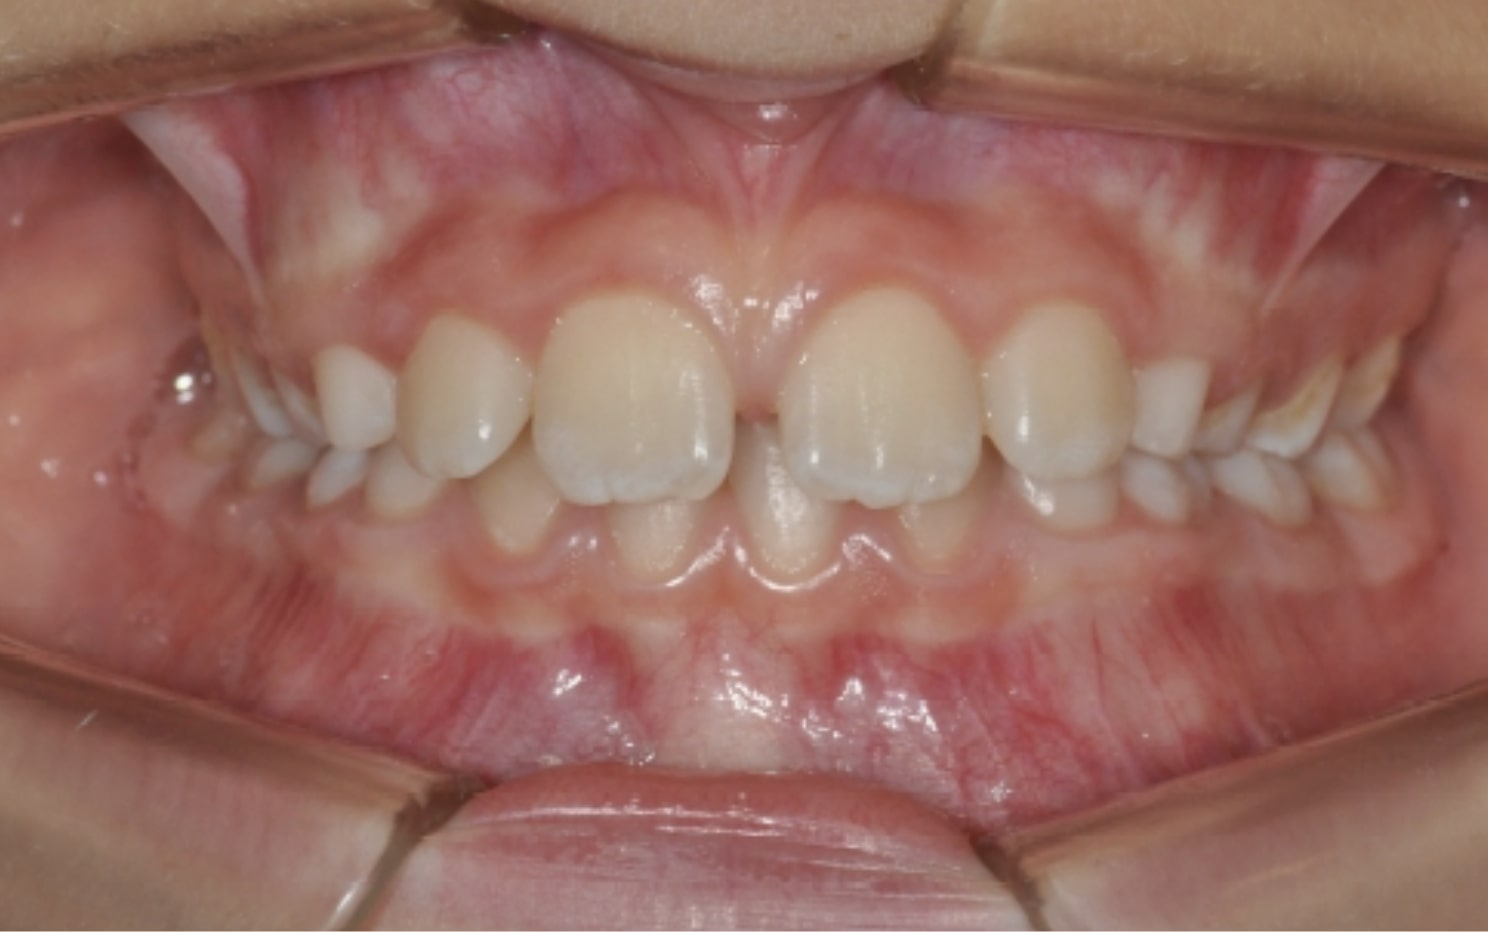

Correction of mandibular retrusion in growing patients with A6 mandibular advancement

By Dr. Giacomo Scuzzo

This case showcases an innovative approach to correcting lower jaw retrusion in growing patients using the Angel Aligner A6. The system combines orthopedic and orthodontic treatment into a single protocol, allowing simultaneous advancement of the lower jaw and alignment of teeth. With digital planning and aesthetic aligners, the treatment is both effective and comfortable for the patient. This case was managed by Dr. Giacomo Scuzzo